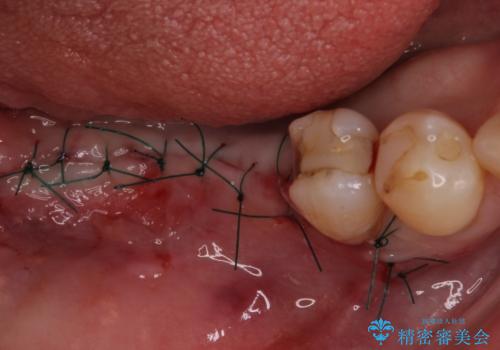

診察したところ、前歯は反対咬合であり、その影響で抜歯が必要な奥歯があることが分かりました。

抜歯が必要な奥歯は、インプラント並びにブリッジにより補綴を行い、上下前歯は反対咬合を改善させるように補綴治療を行うこととしました。

- 外科手術のため、術後に痛みや腫れ、違和感を伴います